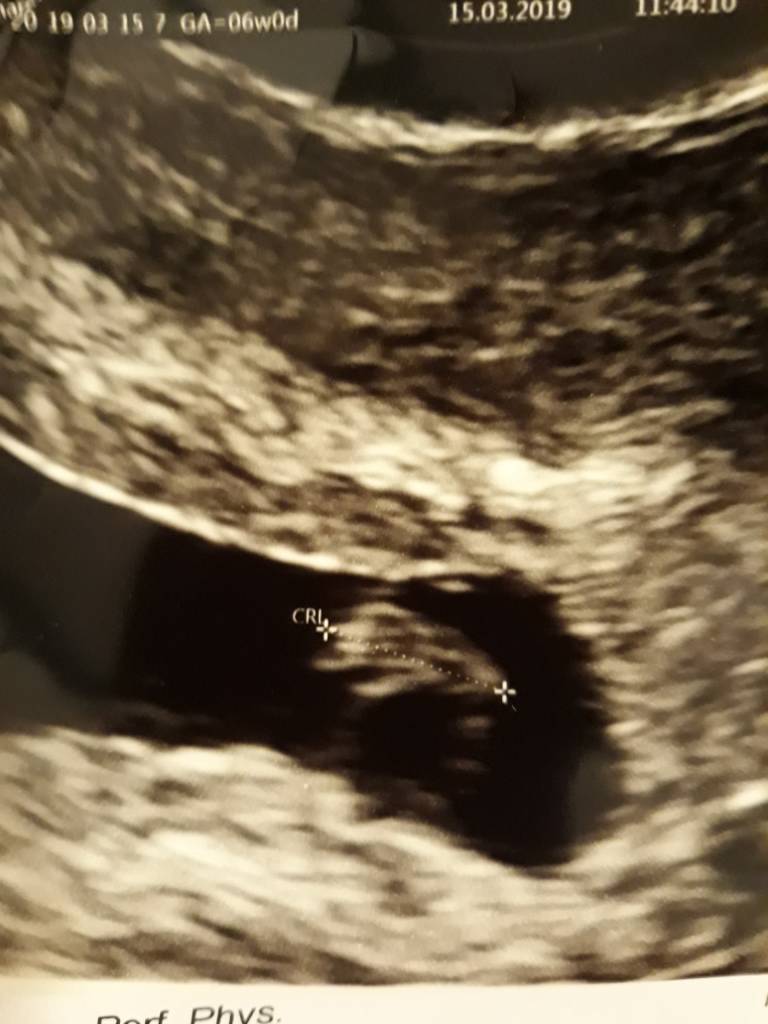

No właśnie nie mam hmm [emoji848] ale to taki sprzęt na NFZ, jakiś kosmiczny nie byłGratulacje, supera masz jakieś oznaczenia na tym USG? Długość zarodka to CRL, GS to chyba pęcherzyk ciążowy, a YS ciałko żółte.

Gratulacje [emoji7][emoji64] jakie u Ciebie wszystko pięknie kształtneU mnie z dzis [emoji3590][emoji3590]

Zobacz załącznik 953041

Z moich obliczeń wynika że 8 tydzień bo liczę od pierwszej miesiączki która była 30 styczniaSuper!!! Który tydzień?

Wyglada jak maly delfinek [emoji16][emoji16][emoji16]Gratulacje [emoji7][emoji64] jakie u Ciebie wszystko pięknie kształtne![]()